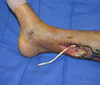

Which of the following conditions is a relative CONTRAINDICATION for use of the flap in the image shown for reconstruction of an 8 x 10-cm anterior ankle wound?

The correct response is Option D.

Diabetes mellitus can be associated with peripheral vascular disease, but by itself, would not prevent successful use of the reverse sural artery flap for foot or ankle reconstruction. Appropriate preoperative workup would include noninvasive ultrasound study of the lower extremity vasculature to prove the peroneal artery was patent.

The distally based sural artery flap receives its blood supply from a few sources, the most robust of which are perforators from the peroneal artery. The most distal of these perforators arise between 4 and 7 cm proximal to the lateral malleolus. Additional perfusion arises from neurocutaneous perforators from the sural nerve and venocutaneous perforators from the lesser saphenous vein.